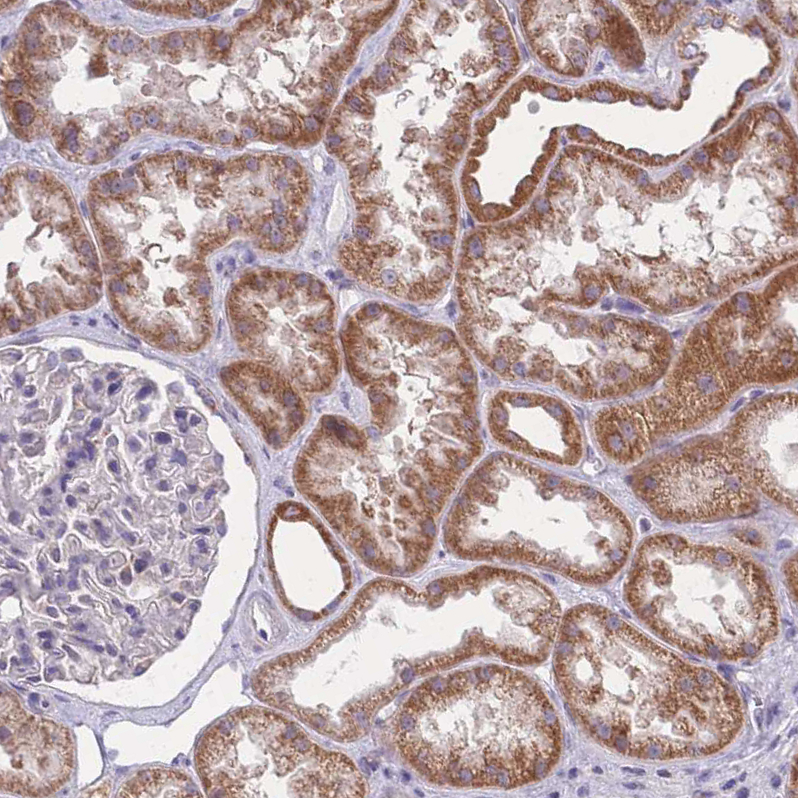

Immunohistochemical staining of human kidney shows moderate granular cytoplasmic positivity in cells in tubules.